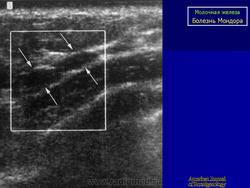

БОЛЕЗНЬ МОНДОРА

При болезни Мондора у больных по ходу сосудов на грудной и брюшной стенке в области молочной железы возникают болезненные, шнуровидные утолщения, иногда протяженностью до 20 см.

Температура тела повышается до субфебрильной. В этот период болезни в венах можно найти тромб, вена расширена, стенки её утолщены. Во второй фазе болезни, которая наступает через 10-14 дней после начала, вена подвергается склерозированию. Кожа, в силу близости к вене и отсутствия между ними фасциальных прослоек вовлекается в воспалительный процесс. Поэтому, при натяжении кожи, особенно при поднятии руки, отведении возникают лучеобразные морщинки по ходу вен.

Болезнь Мондора (Morbus Mondor)

Описана автором в 1939 г и известна также, как string phlebitis. Представляет собой воспалительный процесс, охватывающий v. thoracoepigastrica или v. thoracica lateralis, реже v. epygastrca superficialis по передне-боковой поверхности грудной клетки. В целом патогенез заболевания не выяснен. Некоторые авторы связывали возникновение данной формы тромбофлебита с mastitis vestigial. Существуют предположения об инфекционной и вирусной природе болезни Мондора, поскольку в ряде случаев отмечается увеличение регионарных лимфатических узлов. Встречается преимущественно у женщин среднего возраста, особенно с большими размерами молочной железы и иногда сопутствует неопластическому процессу в последней. В отдельных случаях пальпаторная характеристика тромбированной вены по своей твердости напоминает хорду, что дало основание для еще одного наименования: cord-like phlebitis. Температурная реакция чаще всего отсутствует. Рецидивы практически не наблюдаются. Морфологически обнаруживается облитерирующий эндофлебит.